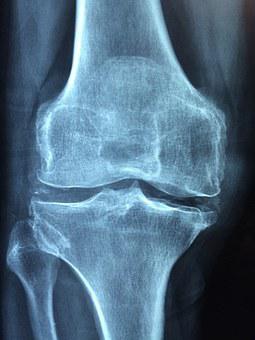

퇴행성 관절염은 관절을 보호하고 있는 연골이 퇴행하거나 점진적인 손상으로 인해 생기는 질환인데요 관절에 염증과 통증이 생기며 특발성관절염과 속발성 관절염으로 분류됩니다

관절염의 원인으로는 부위마다 어느 정도 차이나 나타날 수 있습니다 척추관절염의 경우 직업적으로 반복되는 직업, 생활습관등이 원인이 되며 엉덩이 관절염은 무혈성괴사와 엉덩이관절 이형성증이 대표적인 원인입니다 발목관절염의 경우 골절, 주변인대손상이 가장 흔한 원인입니다 무릎 관절염은 지속해서 무리한 관절 사용으로 인하여 뼈와 뼈 사이에 있는 연골이 닮아서 발생하게 되는데요 손상, 골절, 반월상 연골의 파열, 절제술, 만성 인대장애, 류머티즘성 염증 등과 같은 내과적인 부분으로도 발생합니다

경도의 동통, 피로감, 관절의 운동장애, 종창(붓기), 관절주위의 압통, 운동 중 둔탁한 소리, 골극형성 등이 나타날 수 있습니다

무릎퇴행성관절염 초기에는 무릎 관절 부위에 통증을 느끼거나 관절을 움직일 때 약간의 불편한 마찰음 정도 나는 정도이지만 점점 진행되면서 계단을 오르내리거나 앉았다 일어나는 것들과 같은 일상적인 동작을 할 때 통증이 점점 나타나고 심해집니다